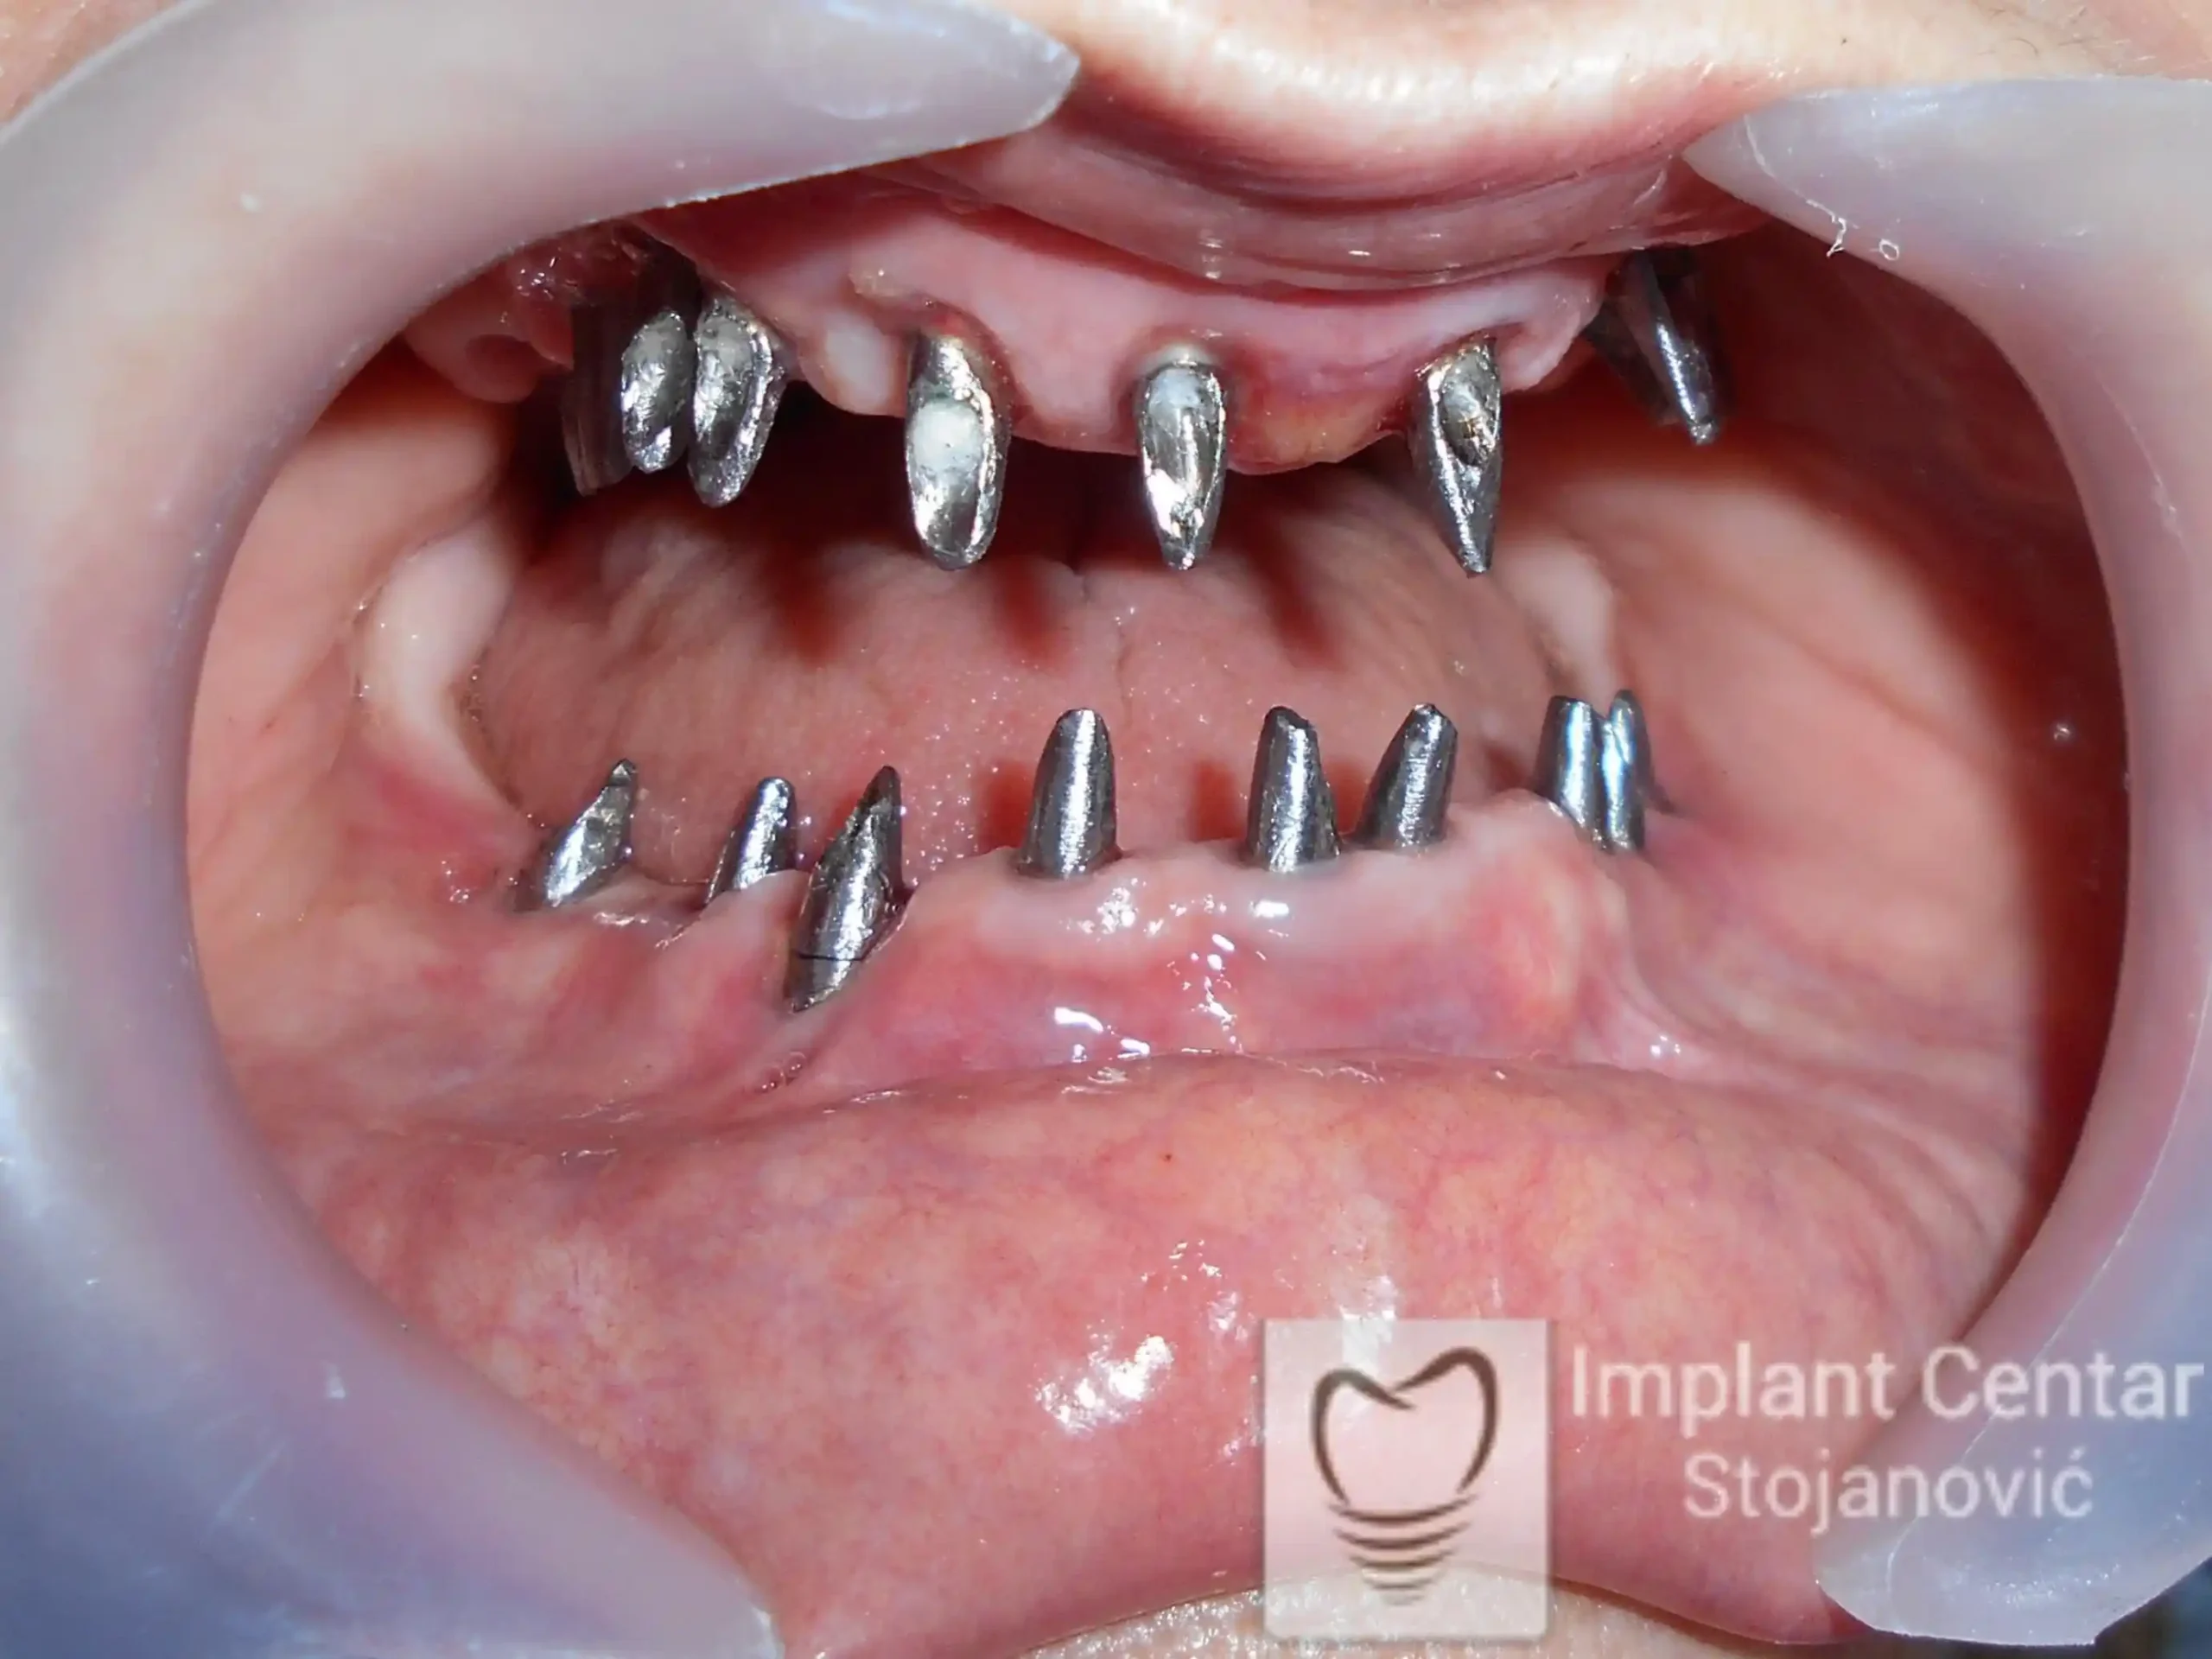

Nakon vađenja zuba, ugrađeni su implantati. Na slici 3 prikazan je ortopan snimak sa ugrđenim implantatima. Tokom perioda osteointegracije, pacijent je bio zbrinut fiksnim privremenim krunicama na implantatima, koje su izrađene samo dva dana nakon hirurške intervencije.

Na slikama 5. i 6. prikazan je izgled definitivnih cirkonijum-keramičkih mostova na implantatima.

Pacijent je izuzetno zadovoljan — kako estetikom novog osmeha, tako i funkcijom, jer ponovo može bez problema da jede i da se smeje.